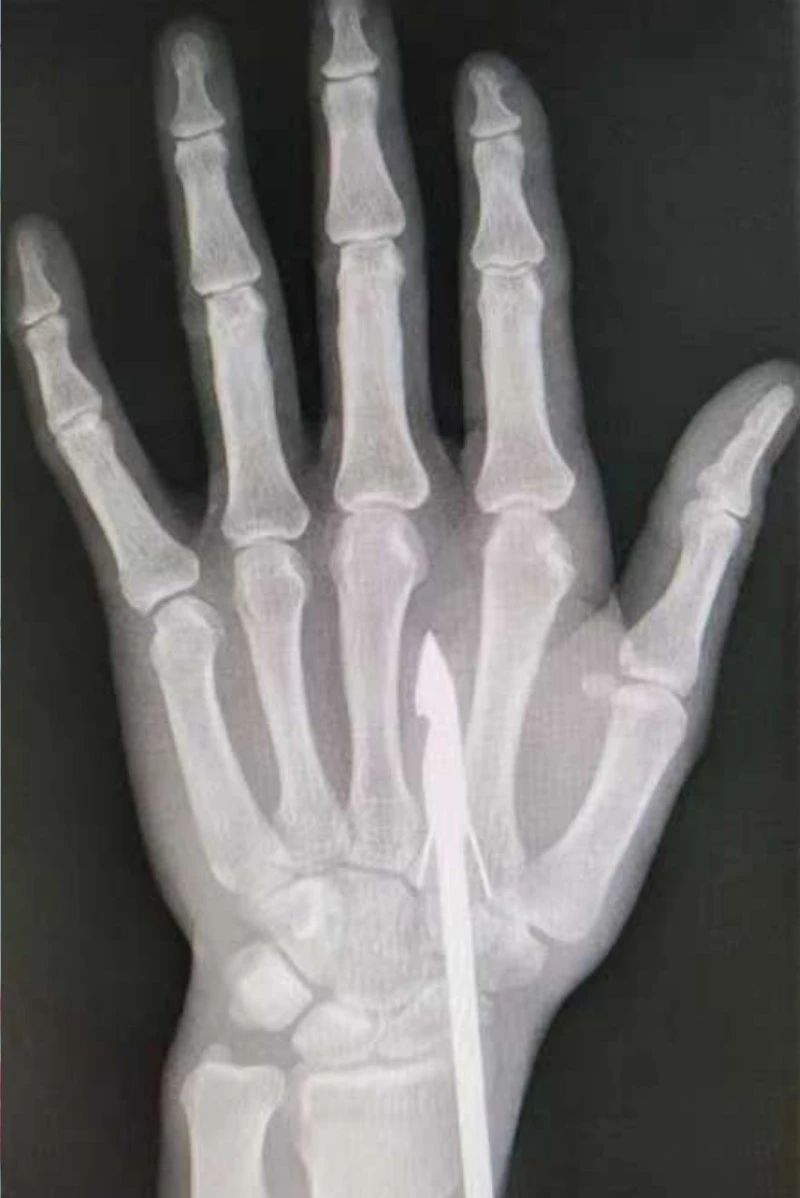

驚險,魚鉤“咬”到手!市骨科醫院手顯微外科巧解決

時間緊迫,每一秒的流逝都可能對傷者的手部功能造成不可逆的損害。接診醫生代彭威,迅速對傷者進行了初步檢查。他注意到,魚鉤已經深深嵌入皮膚,情況遠比表面看起來復雜。沒有絲毫猶豫,立即安排了X線檢查以確認魚鉤的位置及傷及范圍,以及急診化驗檢查以評估患者的整體狀況。

確保在取出魚鉤的同時,不對周圍的組織造成額外的傷害。8點15分左右患者在局部浸潤麻下進行手術,經探查后魚鉤未傷及重要血管、神經及肌腱,經過緊張的十分鐘,魚鉤終于被順利取出,隨后對傷口進行了仔細的清理和縫合,用敷料仔細包扎,確保傷口能夠順利愈合。